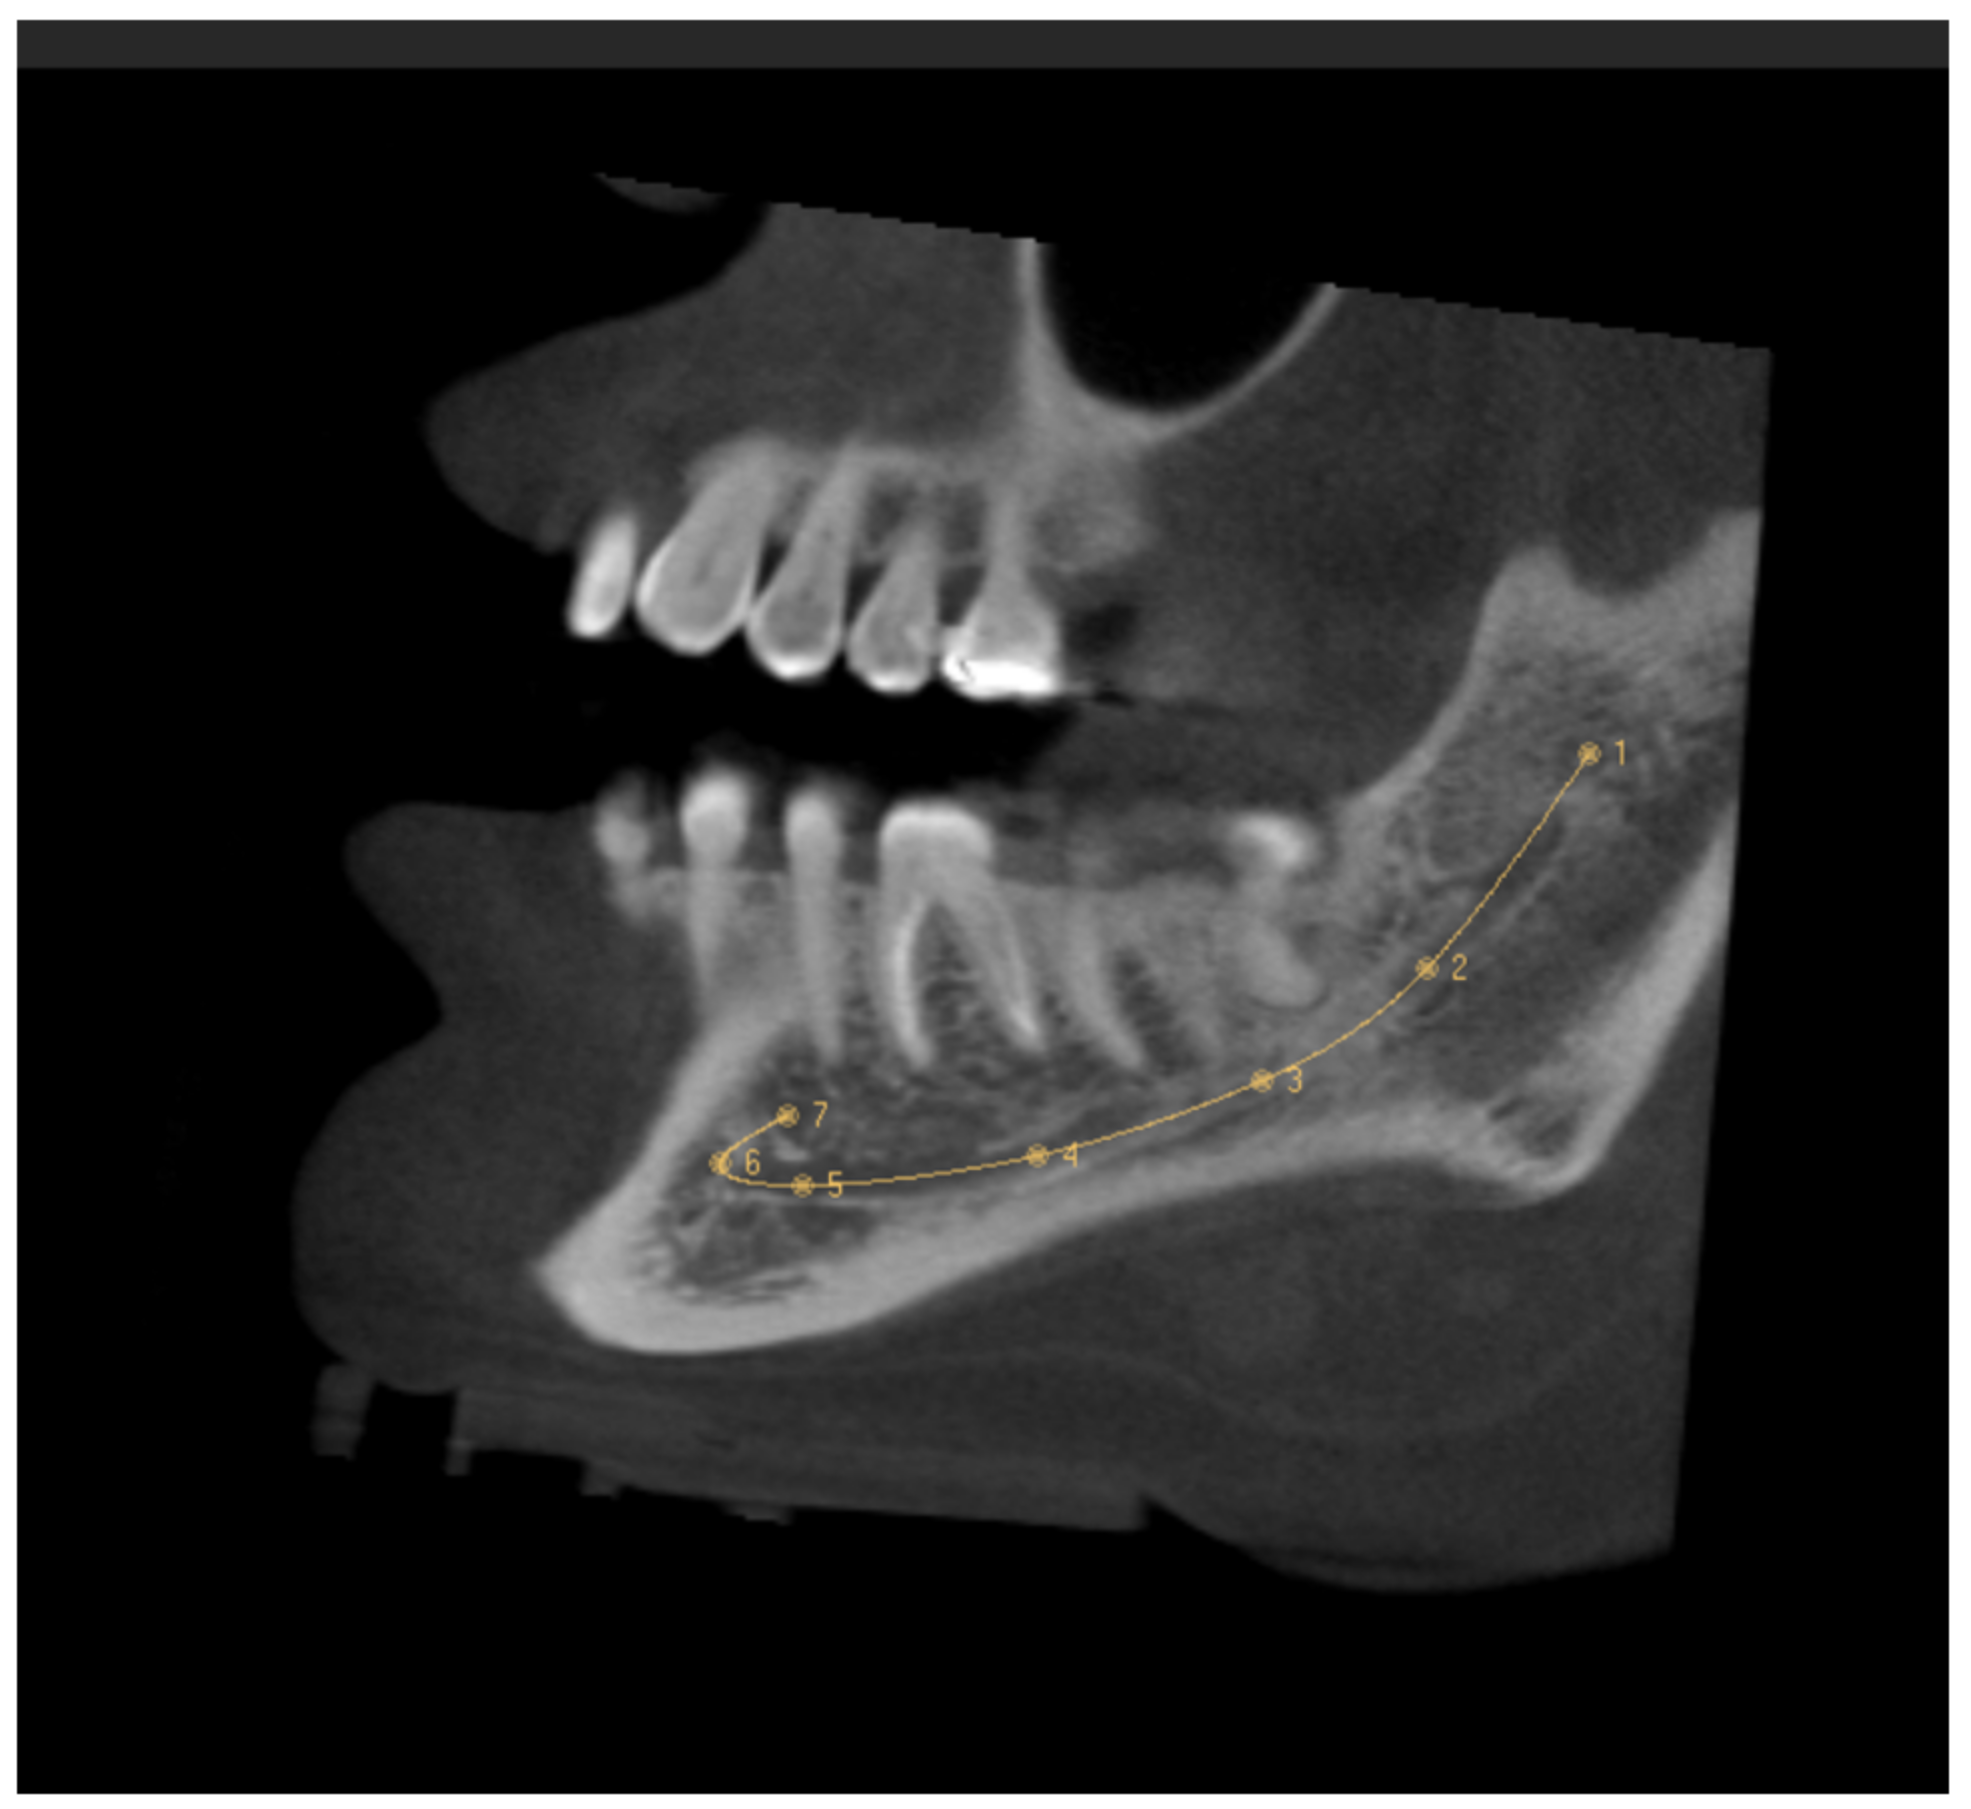

The CBCT study permits longitudinal and oblique rotation of the sections, as well as buccolingual and posteroanterior movements. It was possible to view and analyze the anatomical variants, such as the AL and the RC, using these movements. Once the structures had been identified, their presence was confirmed in every section (Figure 3). The length of the AL was determined by counting the sequential coronal sections from the anterior edge of the MF to the disappearance of the AL, multiplied by the thickness of the section (0.5 mm) (Figure 4).

Figure 3. Sagittal (A), frontal (B), and axial (C) CBCT slides. The red arrow indicates the location of the retromolar canal.